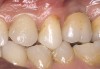

Second-stage surgery was performed after 5 months; healing abutments were placed, and the soft tissue was allowed to heal for an additional 5 weeks. Splinted porcelain-fused-to-metal (PFM) crowns supported by custom gold abutments then were delivered (Figure 5).

Figure 5  Final implant-supported PFM restorations.

Figure 5